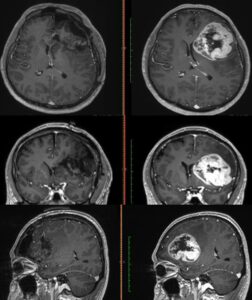

Para determinar la realización de este procedimiento y conocer el origen de los síntomas, explicó, el equipo médico del Instituto le realizó al derechohabiente estudios de tomografía y resonancia magnética.

“Se realizó tomografía de cráneo y, ante los hallazgos, se le practicó una resonancia magnética; posteriormente, se le detectó un tumor de características malignas en la región frontal premotora izquierda”.